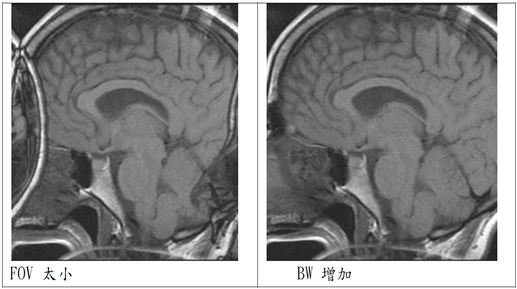

簡單說就是FOV太小,主要發生在相位編碼方向(phase encoding)。

2.增加FOV:FOV增為兩倍來包括所有掃描的範圍,則可將aliasingnartifact消除。